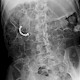

Als Grundlage für Projektionsgesetze geht man von einer punktförmige Strahlenquelle aus, die jeoch in der Realität nicht der Fall ist.

Röntgenstrahlung ist nämlich eine Streustrahlung, dies bedeutet das neben der punktförmigen Strahlenquelle eine Reihe von Streustrahlung links und rechts neben der punktförmigen Strahlenquelle auftreffe. Je grösser die Entfernung wird dest grösser wird der Abstand links und rechts neben der punktförmigen Strahlenquelle. Durch die Hilfe von Blenden, welche sich an der Röntgenröhre befinden un einstellbar sind, können die gewünschte bestrahlungsbereiche jedoch relativ gut eingegrenzt werden. Außerdem geht man von einer gradlinigen Divergenz der Strahlen aus. Diese Theorie ist ebenfalls nur eine Vereinfachung.